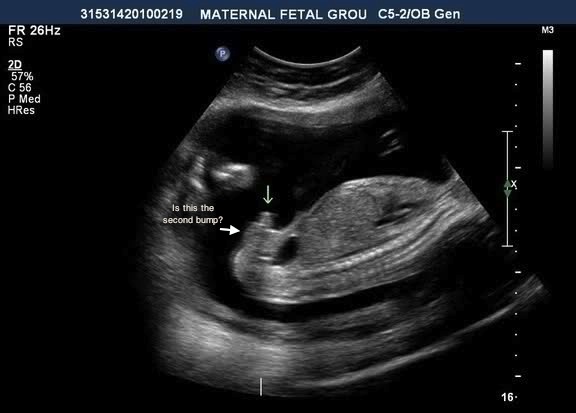

This is at 15 weeks...getting mixed reviews of boy and girl. No potty shot but looked to be nothing down there when the tech looked, just the nub on profile. Thanks :)

Hmmm- by 15 weeks I don't think there is a nub anymore. So I'm going to guess this is a boy

I would vote boy on the top picture.

15 weeks is to late for a nub guess, you need a potty shot!! It does look rather like a boy though!

I don't have any potty shots because the tech didn't print them out. She insisted this stage was too early although I did not see anything protruding on the potty shot so when I saw the "nub" on profile I was confused. Other techs have been telling me a prominent clitoris is common at 15 weeks and that the angle of my babies nub looks girly as well as the shape but I'm still not sure :think:

I have seen this type of question posted a number of times on IG. The tech there always says that you can clearly see a penis and scrotum pointing straight up at 15 weeks, and that profiles are a great way to identify sex, particularly before the baby gets too squished (so, you definitely don't need a potty shot to identify sex). Even if you look at the last pictures on the site below (which are 14 weeks), yours is almost identical to the girl picture: Embryo Development external genital sex organs - angle of the dangle boy or girl ultrasound gender scan - Baby2see

Personally, I would see check out 15 week ultrasounds on youtube, and I think that you will find that the boy profiles look very different ;)